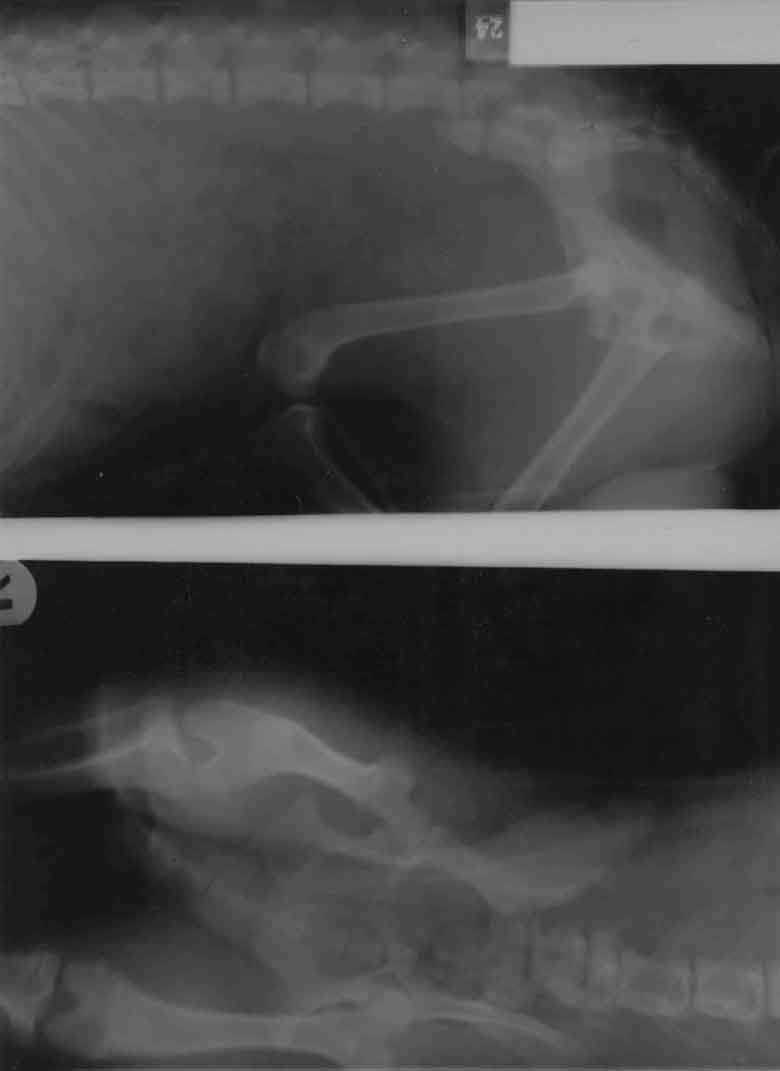

Hüftgelenksluxation

Toggle Pin - Anker - Fixation